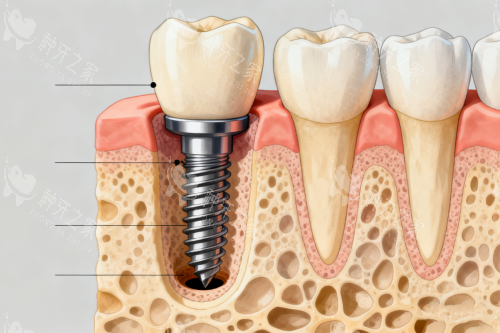

种植牙,作为当下修复牙齿缺失的理想方式,是将人工牙根(种植体)比较准植入牙槽骨内,再安装牙冠,以此替代缺失的牙齿。它宛如 “再生牙齿”,具有诸多优势。与传统假牙相比,种植牙无须磨除相邻的天然牙,对健康邻牙毫无损伤;固位结果较好,人工牙根与骨组织形成紧密的骨结合,稳固性强;能比较大限度地改善牙齿的咬合功能,几乎接近天然牙;异物感极小,舒适感仿若天然牙;美观度高,不会造成发音和咀嚼障碍;还可对牙槽骨产生功能性刺激,有效防止牙槽骨失用性吸收,维持牙龈健康。若维护得当,种植牙的使用寿命甚至可伴随一生。

接着是植入种植体,恰似用钢筋水泥浇筑地基。在局麻或静脉麻醉下,医生将钛合金种植体比较准植入牙槽骨,如同 “埋入地基钢筋”。部分机构会采用 AI 动态导航技术,避开神经血管,误差小于 0.1 毫米。若骨条件良好,拔牙后可立即植入种植体,缩短治疗周期。植入后,医生会对仅 3 - 5 毫米的切口进行缝合,术后 1 - 2 周拆线。

然后是骨结合阶段,如同水泥静置养护。种植体与牙槽骨需 3 - 6 个月完成 “骨结合”,形成稳固的人工牙根。在此期间,前牙区可安装临时义齿,不影响美观和进食。不过,吸烟、糖尿病等因素可能会延长愈合时间,患者需严格遵医嘱。

之后是安装基台,好比搭建房屋主体结构。骨结合完成后,医生会切开牙龈暴露种植体,安装愈合基台,1 - 2 周后牙龈形态改善自然,为牙冠提供理想 “底座”。

然后是佩戴牙冠,如同房屋的精装修。医生会通过智能化扫描或传统取模,制作个性化牙冠,材质可选全瓷或烤瓷。全瓷冠通透逼真,适合前牙;烤瓷冠耐磨经济,适合后牙。安装牙冠时,医生会调整咬合高度、邻接关系,确保患者咀嚼舒适。